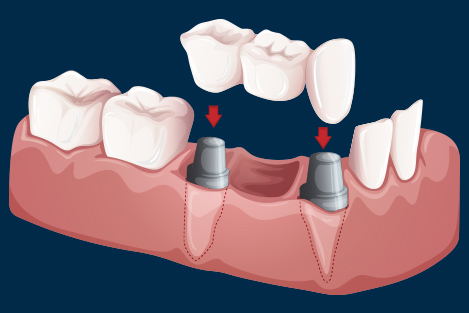

5. Fixed teeth (crown and bridges)

A bridge is a fixed dental restoration (a fixed dental prosthesis) used to replace a missing tooth (or several teeth) by joining an artificial tooth permanently to adjacent teeth or dental implants.

A crown is a type of dental restoration which completely caps or encircles a tooth or dental implant. Crowns are often needed when a large cavity threatens the ongoing health of a tooth.They are typically bonded to the tooth using a dental cement. Crowns can be made from many materials, which are usually fabricated using indirect methods. Crowns are often used to improve the strength or appearance of teeth. While inarguably beneficial to dental health, the procedure and materials can be relatively expensive.